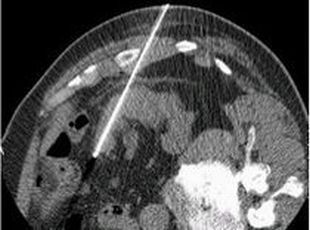

また腎臓がんの治療は手術が中心になりますが、腎実質に存在し腫瘍径が小さい(直径4cm以下)腎臓がんに対しては、

積極的に経皮的局所療法である腎ラジオ波焼灼術(腎 RFA:radiofrequency ablation)を施行しています。

詳細はRFAのページをご覧ください。

腎 RFA